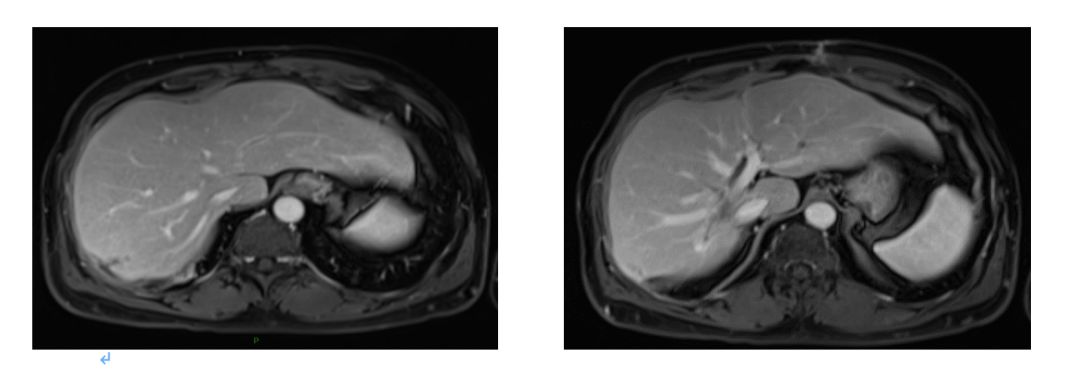

2015.1.22 肝脏MRI:肝右叶后段至尾叶肿块(大小4.9cm*5.9cm*5.4cm),肝右前叶近膈面0.9cm结节影,增强扫描边缘明显强化。

影像学评估 2015.4.7;

4周期评估肿瘤部分缩小;

影像学评估:8周期化疗后,肝脏病灶缩小43%,疗效评价为部分缓解(PR)。

2016.4.28肝脏MRI:治疗后改变。